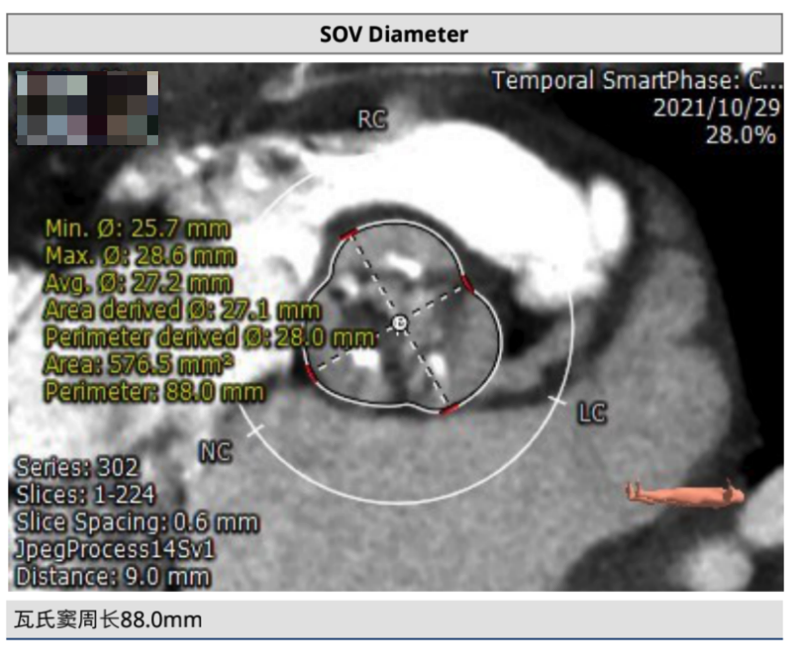

主动脉CT

该患者瓣环与水平成角常规;

瓣环周长:62.8mm;

流出道直径:19mm;

左侧冠脉开口较低;

左右无冠窦较宽;

窦管结合部直径26.2mm及高度17.66mm。

建议20mm球囊,TAV21瓣膜,备TAV24瓣膜。左冠高度7.7mm,开口高度低,瓣叶长,窦宽小,右无有钙化粘连,左冠风险高。右冠高度12.2mm,开口高度低,瓣叶长,窦宽小,右冠风险高。建议双侧冠脉保护及球扩评估。